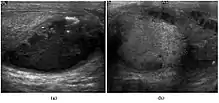

Teratoma Although teratoma is the second most common testicular tumor in children, it affects all age groups. Mature teratoma in children is often benign, but teratoma in adults, regardless of age, should be considered malignant. Teratomas are composed of all three germ cell layers, i.e. endoderm, mesoderm and ectoderm. At ultrasound, teratomas generally form well-circumscribed complex masses. Echogenic foci representing calcification, cartilage, immature bone and fibrosis are commonly seen [Fig. 5]. Cysts are also a common feature and depending on the contents of the cysts i.e. serous, mucoid or keratinous fluid, it may present as anechoic or complex structure [Fig. 6].

Fig. 6. Mature cystic teratoma. (a) Composite Image. Mature cystic teratoma in a 29-year-old man. Longitudinal sonography image of the right testis shows a multilocular cystic mass. (b) Mature cystic teratoma in a 6-year-old boy. Longitudinal sonography of the right testis shows a cystic mass containing calcification with no obvious acoustic shadow.